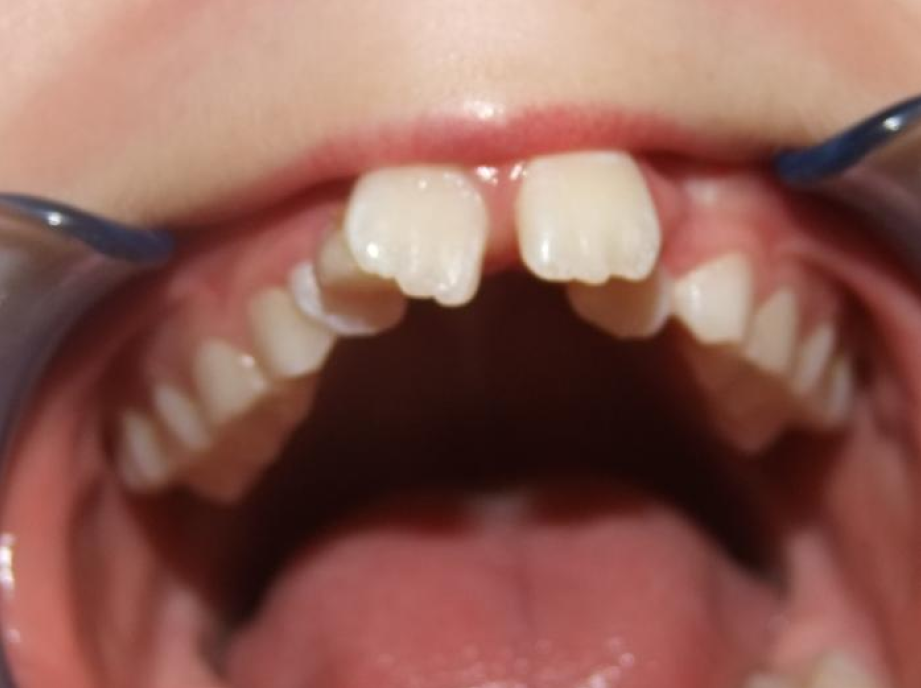

1-6 Bonded Hyrax + volledig vast onderkaak + TransForce onderkaak

7-13 Twin Block

14-28 volledig vast onder- en bovenkaak + rotator

Retentie: Wrap-Around

Leeftijd bij retentie: 12 jaar